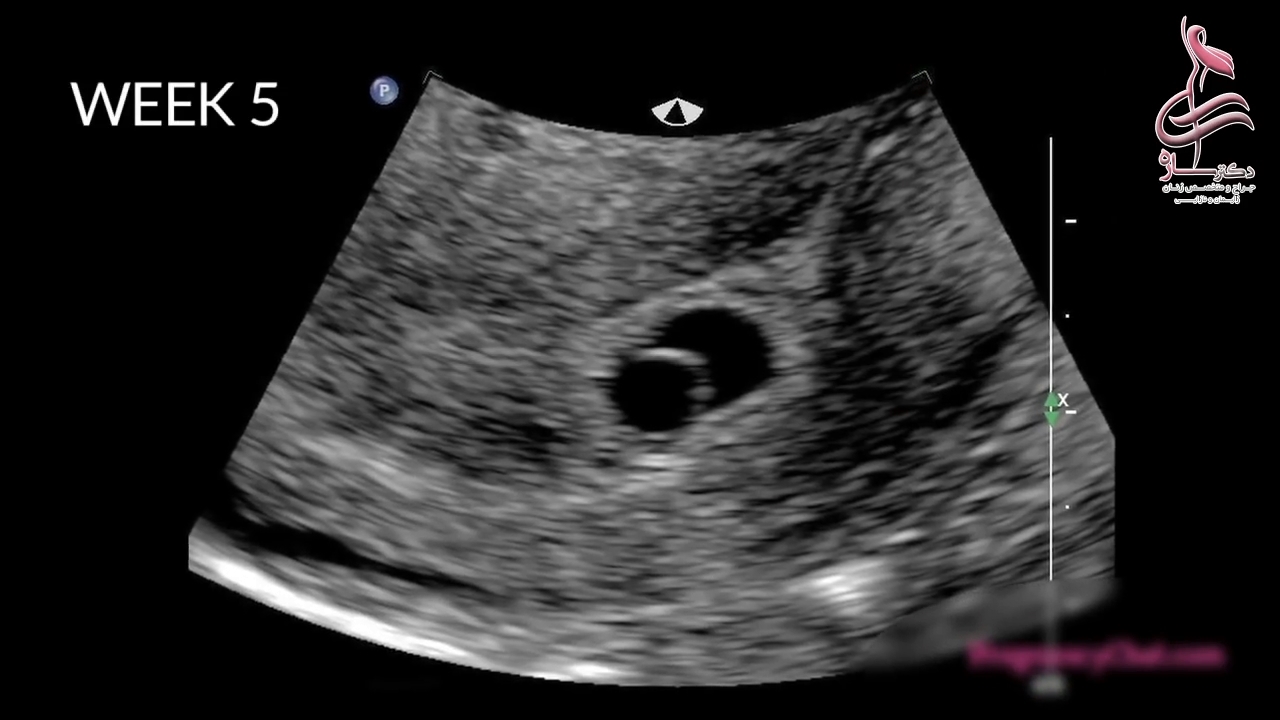

پخش صدا ۹ ماه زندگی جنین در رحم را در یک دقیقه ببینید اشتراکگذاری لیست پخش ۰ نظر ۰ نظر دانلود دانلود ویدیو دانلود کیفیت 720p ۹.۸۶ مگابایت دانلود کیفیت 480p ۸.۱۳ مگابایت دانلود کیفیت 360p ۵.۷۲ مگابایت دانلود کیفیت 240p ۳.۵۱ مگابایت دانلود کیفیت 144p ۲.۱۱ مگابایت گزارش تخلف بیشتر گزینههای بیشتر لیست پخش لایکها گزارش تخلف ۰ لایک دکتر ساره حیدری منتشر شده در تاریخ ۱۴۰۰/۱۲/۲۸ این کانال دنبال شد دنبال کردهاید دنبال کردن این کانال دنبال کردن جراح و متخصص زنان،لیزر،زیبایی زنان ادامه نظرات لبخند لبخند لغو ثبت نظری برای نمایش وجود ندارد.